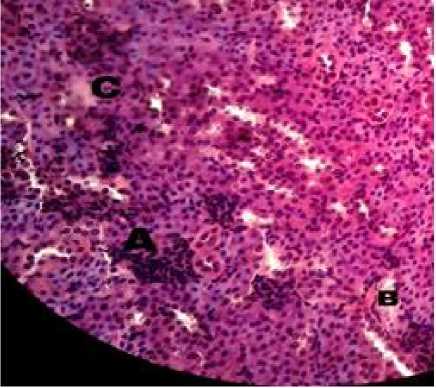

Gambar 4. Gambaran histopatologi ginjal mencit (Mus musculus) P3 (HE, 400×). Terlihat adanya perdarahan (A), nekrosis.(B), dan degenerasi melemak (C).

Lesi degenerasi melemak pada kelompok kontrol dan ekstrak sarang semut, dosis 100 mg/kg BB, dan 200 mg/kg BB tidak tampak. Hal ini menunjukkan bahwa sampai dosis 200 mg/kgBB tidak terjadi gangguan metabolisme pada sel tubulus ginjal. Tetapi pada pemberian ekstrak etanol sarang semut dosis 300 mg/kg BB tampak ada lesi degenerasi melemak. Lesi ini menandakan adanya gangguan metabolisme pada sel tubulus ginjal akibat toksisitas.

Lesi nekrosis pada pemberian ekstrak etanol sarang semut dosis 100 mg/kg BB dan 300 mg/kg BB tampak sama, tetapi lesi nekrosis sedikit pada dosis 200 mg/kgBB. Hal ini mungkin berkaitan dengan penggunaan mencit yang tidak Spesific Pathogen Free (SPF). Nekrosis atau kematian sel adalah kerusakan lanjutan dari degenerasi parenkimatosa yang bersifat irreversibel. Proses kematian sel berlangsung lebih cepat daripada proses regenerasi, sehingga sel-sel mati terakumulasi pada jaringan. Sel yang mati dikenali tubuh sebagai benda asing, sehingga sel mati tersebut selalu dikelilingi oleh sel-sel radang. Jaringan nekrosis

secara mikroskopik akan mengalami

berbagai perubahan berupa piknosis,

karyorheksis, ataupun karyolisis (Berata et al, 2011).